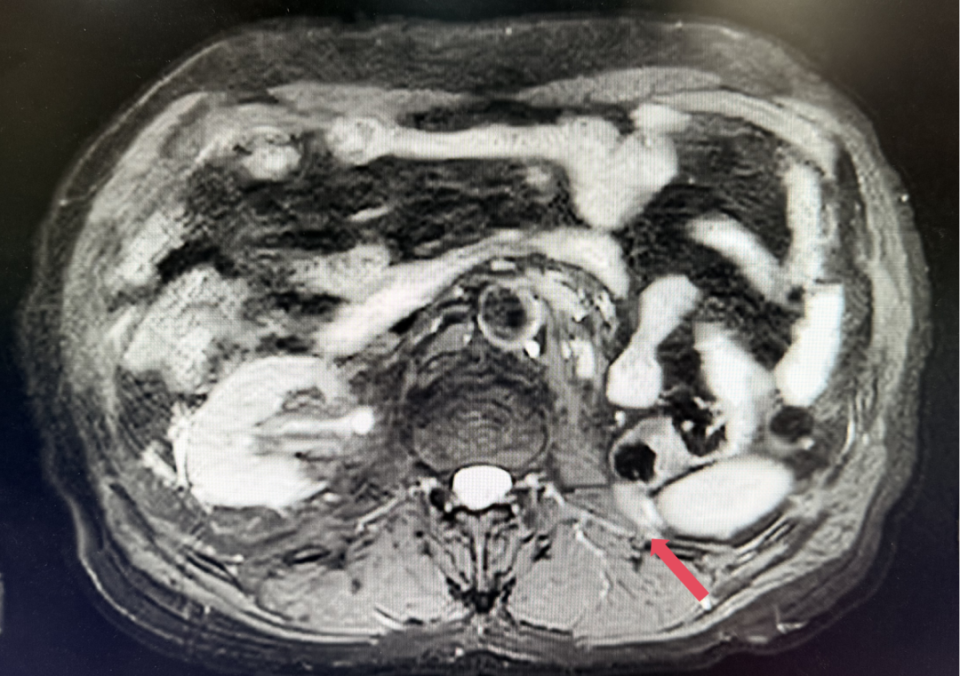

2023年1月,基线

2022年3月:患者因“左腰痛”复查。胸部CT提示双肺微小结节,较前未见明显变化;腹盆MR示:左侧腹膜后多发结节及肿块影,较大者约5.7cm*5.1cm;考虑患者诊断为转移性肾透明细胞癌,IV期,IMDC评分0分,低危组。予培唑帕尼一线治疗8个月,最佳疗效SD。

2022年11月:MR示左侧腹膜后多发结节及肿块影,较前略增大,6.1*5.5cm,另可见邻近左侧后腹膜多发DWI异常信号结节,较前新发,较大者2.4*2.1cm,考虑疾病进展(PD)。